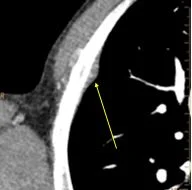

Conventional CT: Pleural based nodule (yellow arrow).